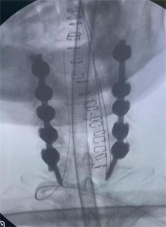

8. 机器人导航辅助下脊柱侧弯矫正技术

脊柱侧弯是一种复杂的脊柱三维畸形,其中以青少年特发性脊柱侧凸最常见。我院在浦口地区率先开展机器人导航辅助下脊柱侧弯矫正术,实现了脊柱侧弯手术准确、微创、智能化的突破,获得了良好的效果。还有老年人退变性侧弯,机器人亦可精准置入困难椎弓根螺钉,误差只有0.3mm。